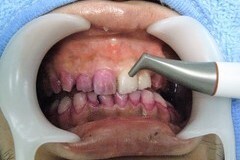

5.定期的リコールの開始 歯周病、虫歯に対する口腔内診査と予防処置、補綴物のチェック 歯科医が行う当クリニックでの歯周処置「プロフェッショナルクリーニング」と虫歯予防処置「フッ素塗布」 |